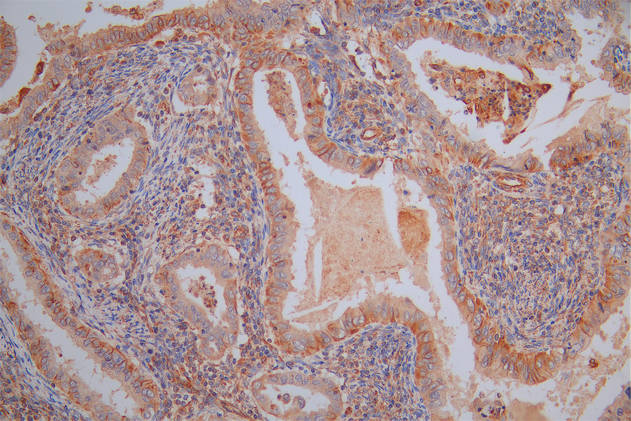

The image on the left is immunohistochemistry of paraffin-embedded Human gastic cancer tissue using CSB-PA196653(ABI1 Antibody) at dilution 1/40, on the right is treated with synthetic peptide. (Original magnification: ×200)

The image on the left is immunohistochemistry of paraffin-embedded Human brain tissue using CSB-PA196653(ABI1 Antibody) at dilution 1/40, on the right is treated with synthetic peptide. (Original magnification: ×200)